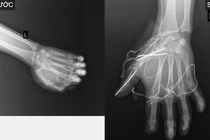

Tai nạn do pháo nổ không chỉ gây tổn thương phần mềm, dập nát bàn tay, gãy xương phức tạp mà còn bỏng gây di chứng tàn phế vĩnh viễn.